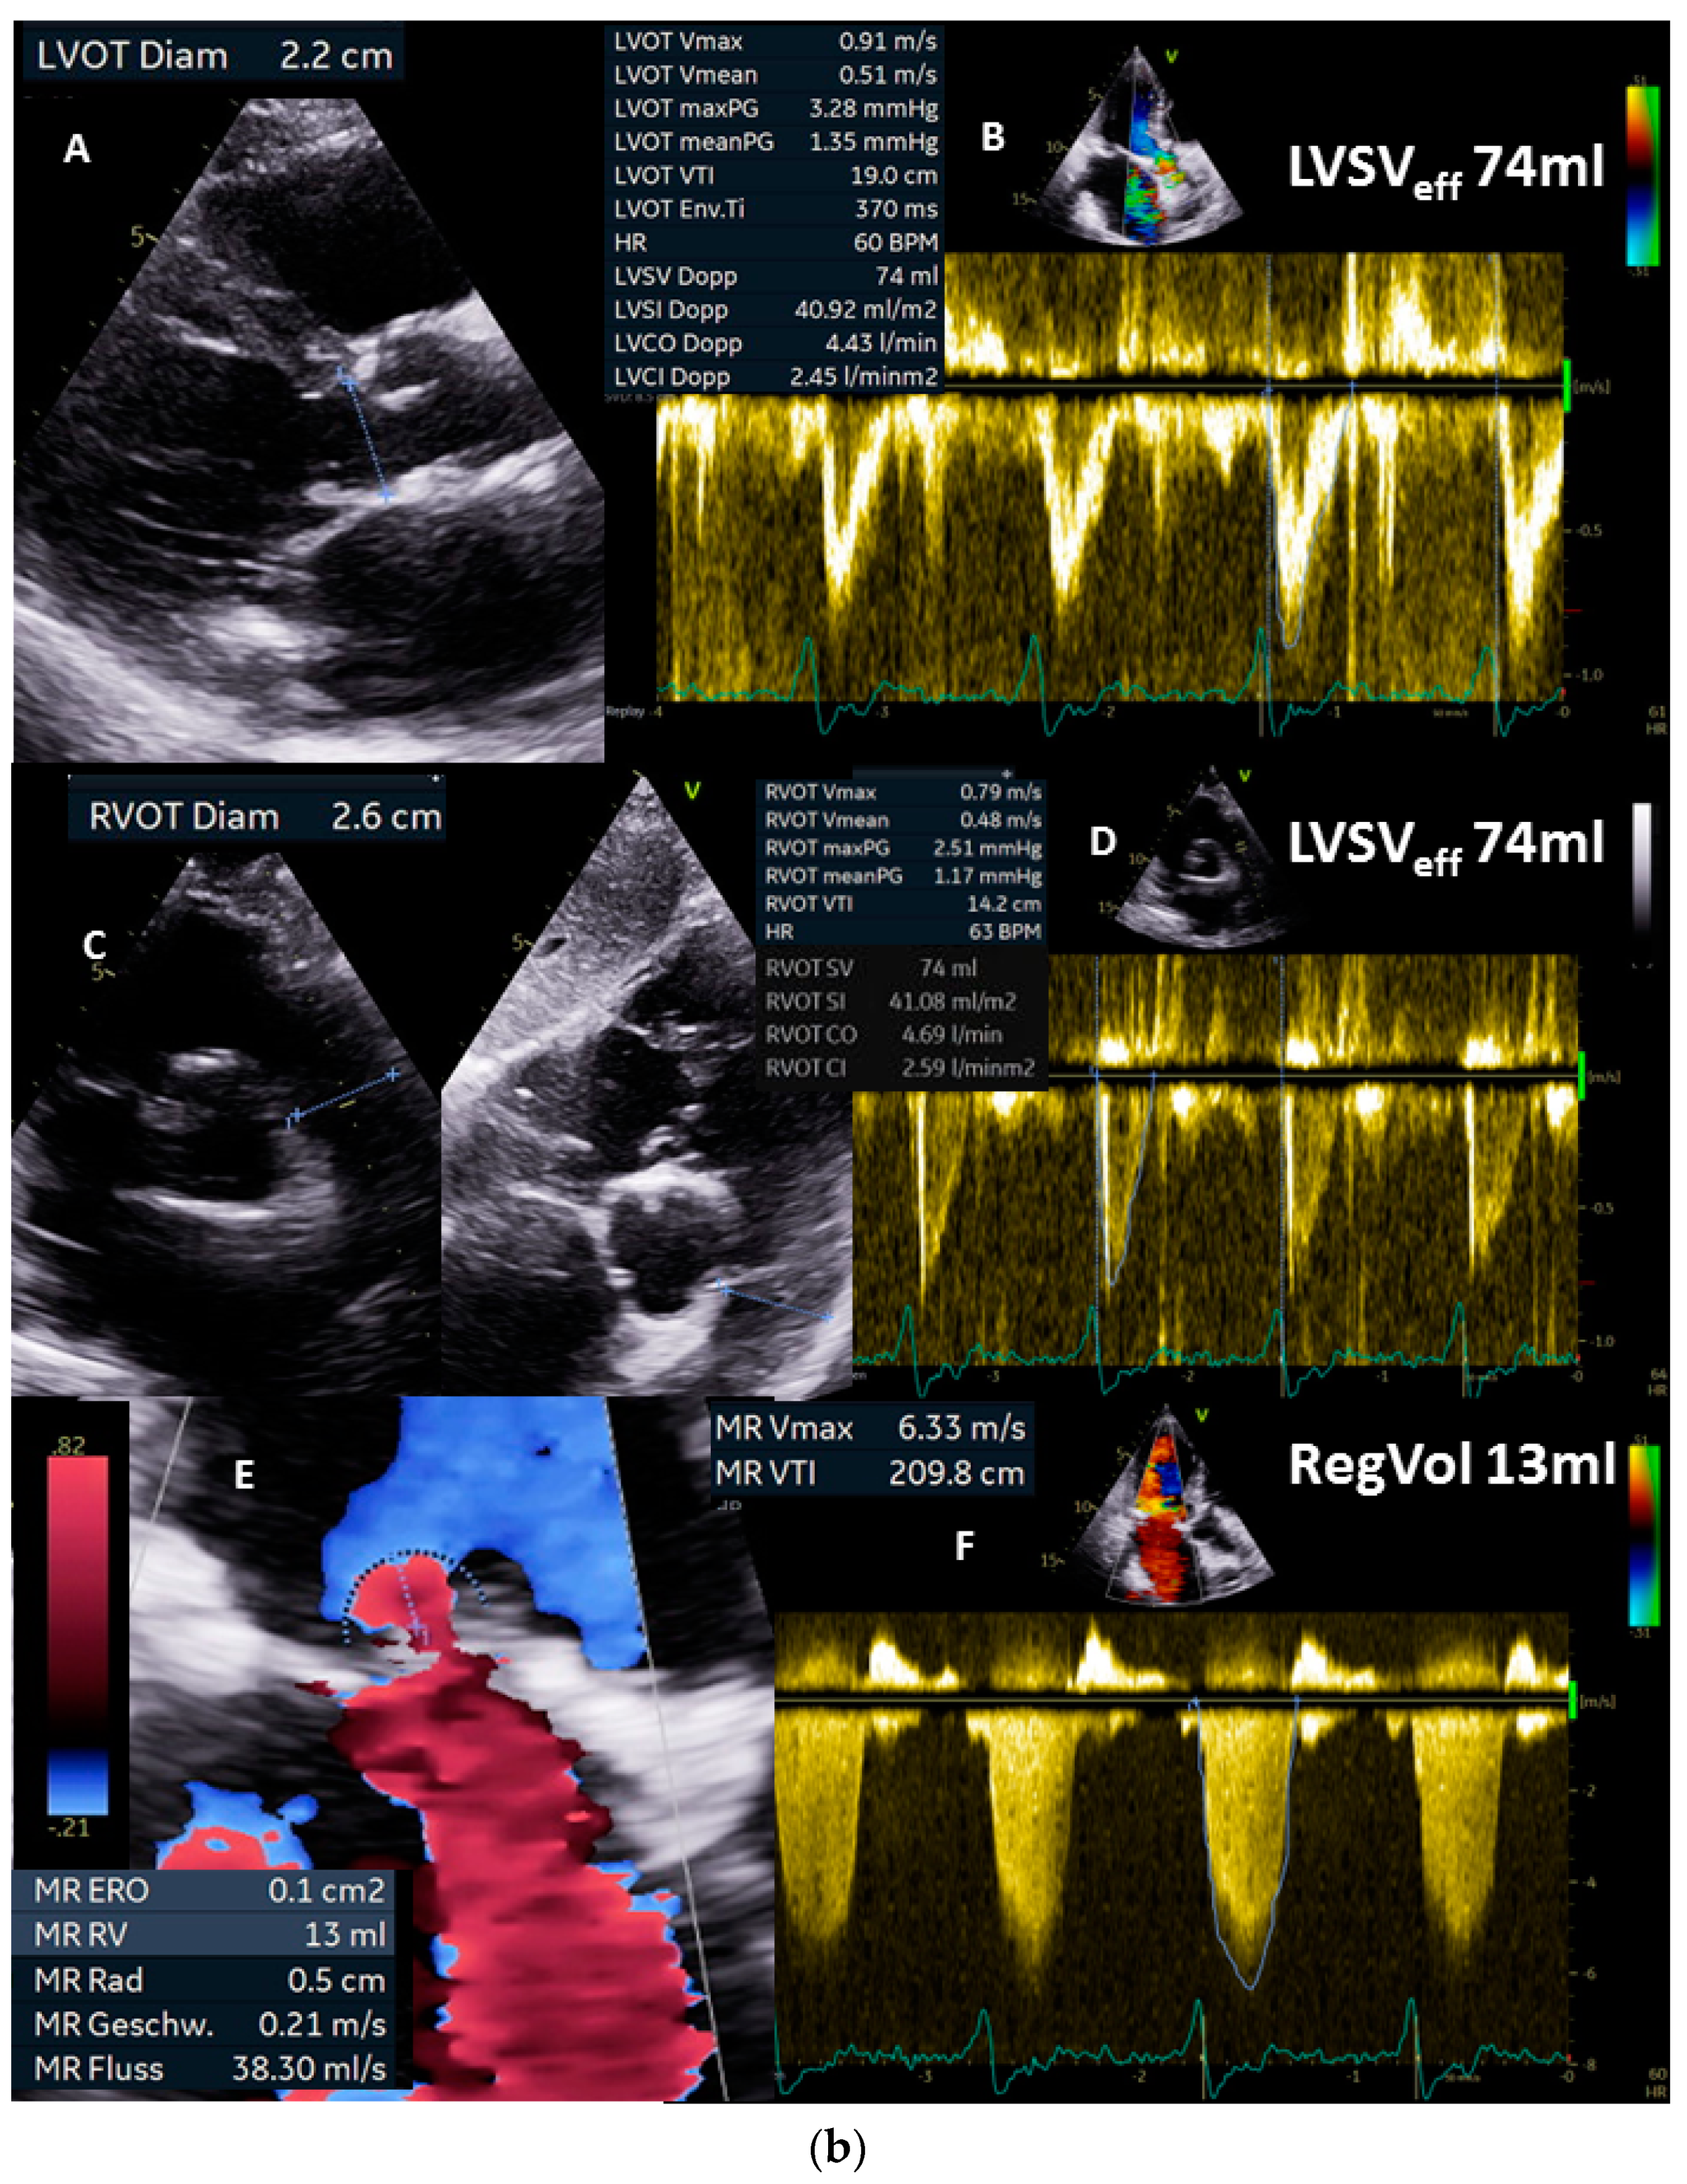

(a): Illustration of a systolic regurgitant jet phenomenon in a patient with isolated mitral regurgitation and the quantitative analysis of left ventricular volume parameters. In (A), the small vena contracta < 1 mm despite a remarkable jet area is shown. In (B), monoplane LV planimetry is shown using the apical long-axis view. In (C), the biplane LV planimetry is shown documenting a total LVSV of 90 mL. In (D), a color-coded M-Mode through the MR shows a nearly constant PISA radius. In (E), the cw regurgitant Doppler velocity is shown. LVEDV = left ventricular end diastolic volume, LVESV = left ventricular end systolic volume, LVSV = left ventricular stroke volume, LVSVtot = total LVSV, and LVEF = left ventricular ejection fraction. (b): Illustration to assess quantitatively effective LVSV and RVSV by pw Doppler echocardiography as well as regurgitant volume by 2D PISA method to analyze severity of mitral regurgitation (MR): in (A), the parasternal long-axis to document LVOT diameter during systole is shown; in (B), the measurements of LVSVeff by pw Doppler spectrum at the level of the LVOT is shown; in (C), the parasternal and subcostal short-axis views are shown to document RVOT diameter during systole; in (D), the measurements of RVSVeff by pw Doppler spectrum at the level of the RVOT is shown. The estimation of RegVolMR by 2D PISA is demonstrated by delineation of the 2D-PISA radius and the velocity time integral of the retrograde transmitral velocity during systole (E,F). LVSV = left ventricular stroke volume, LVEF = left ventricular ejection fraction, LVSVeff = effective LVSV, RegVol = transmitral regurgitant volume, LVOT = left ventricular outflow tract, RVOT = right ventricular outflow tract.

Figure 4.

At this point in the examination, the findings should be checked for hemodynamic plausibility. Calculating the minimum effective LVSV to enable a required effective CO and CI at a heart rate of 63/min (corresponding to values of approximately CO = 4 L/min; CI = 2.2 L/min m2: 4000 mL/min/63/min = 63 mL) facilitates the interpretation. Thus, the maximum possible RegVolMR to be above shock limit is (90 mL − 63 mL = 27 mL), which corresponds to a RF of 30%.

Next, the effective LVSV should be quantified by Doppler echocardiography (Figure 4b(A,B)—pw-Doppler LVOT, Figure 4b(C,D)—pw-Doppler RVOT), yielding approximately 75 mL (Figure 4b(E,F)). Thus, RegVolMR was 15 mL in this case. RegVolMR can additionally be checked by 2D PISA method if there are no methodological limitations to the use of 2D PISA method (Figure 4a(D)—color-coded M-Mode—MR, Figure 4a(E)—cw-Doppler—MR, Figure 4b(E,F)—2D PISA method). Thus, RFMR was less than 20% in this case. In conclusion, secondary alterations, e.g., increased E/e’ ratio and/or increased systolic pulmonary arterial pressure, associated with relevant MR, should be considered to exclude high-grade MR.

In summary, this example documents mild functional MR confirmed by clinical presentation without symptoms, normal ranges of LVEDV and LVEF, and individual mild-grade RFMR < 20% at a calculated effective CO and CI of 4.7 L/min and 2.6 L/ min m2, respectively.

The reliability of the echocardiographic volume measurements in this case of a pure mitral regurgitation can be counterchecked by the determination of effective LVSV and RVSV. In addition, the total LVSV must be the sum of effective LVSV and RegVolMR. The calculated RegVolMR can be checked in this case by the determination of RegVolMR by the 2D PISA method.